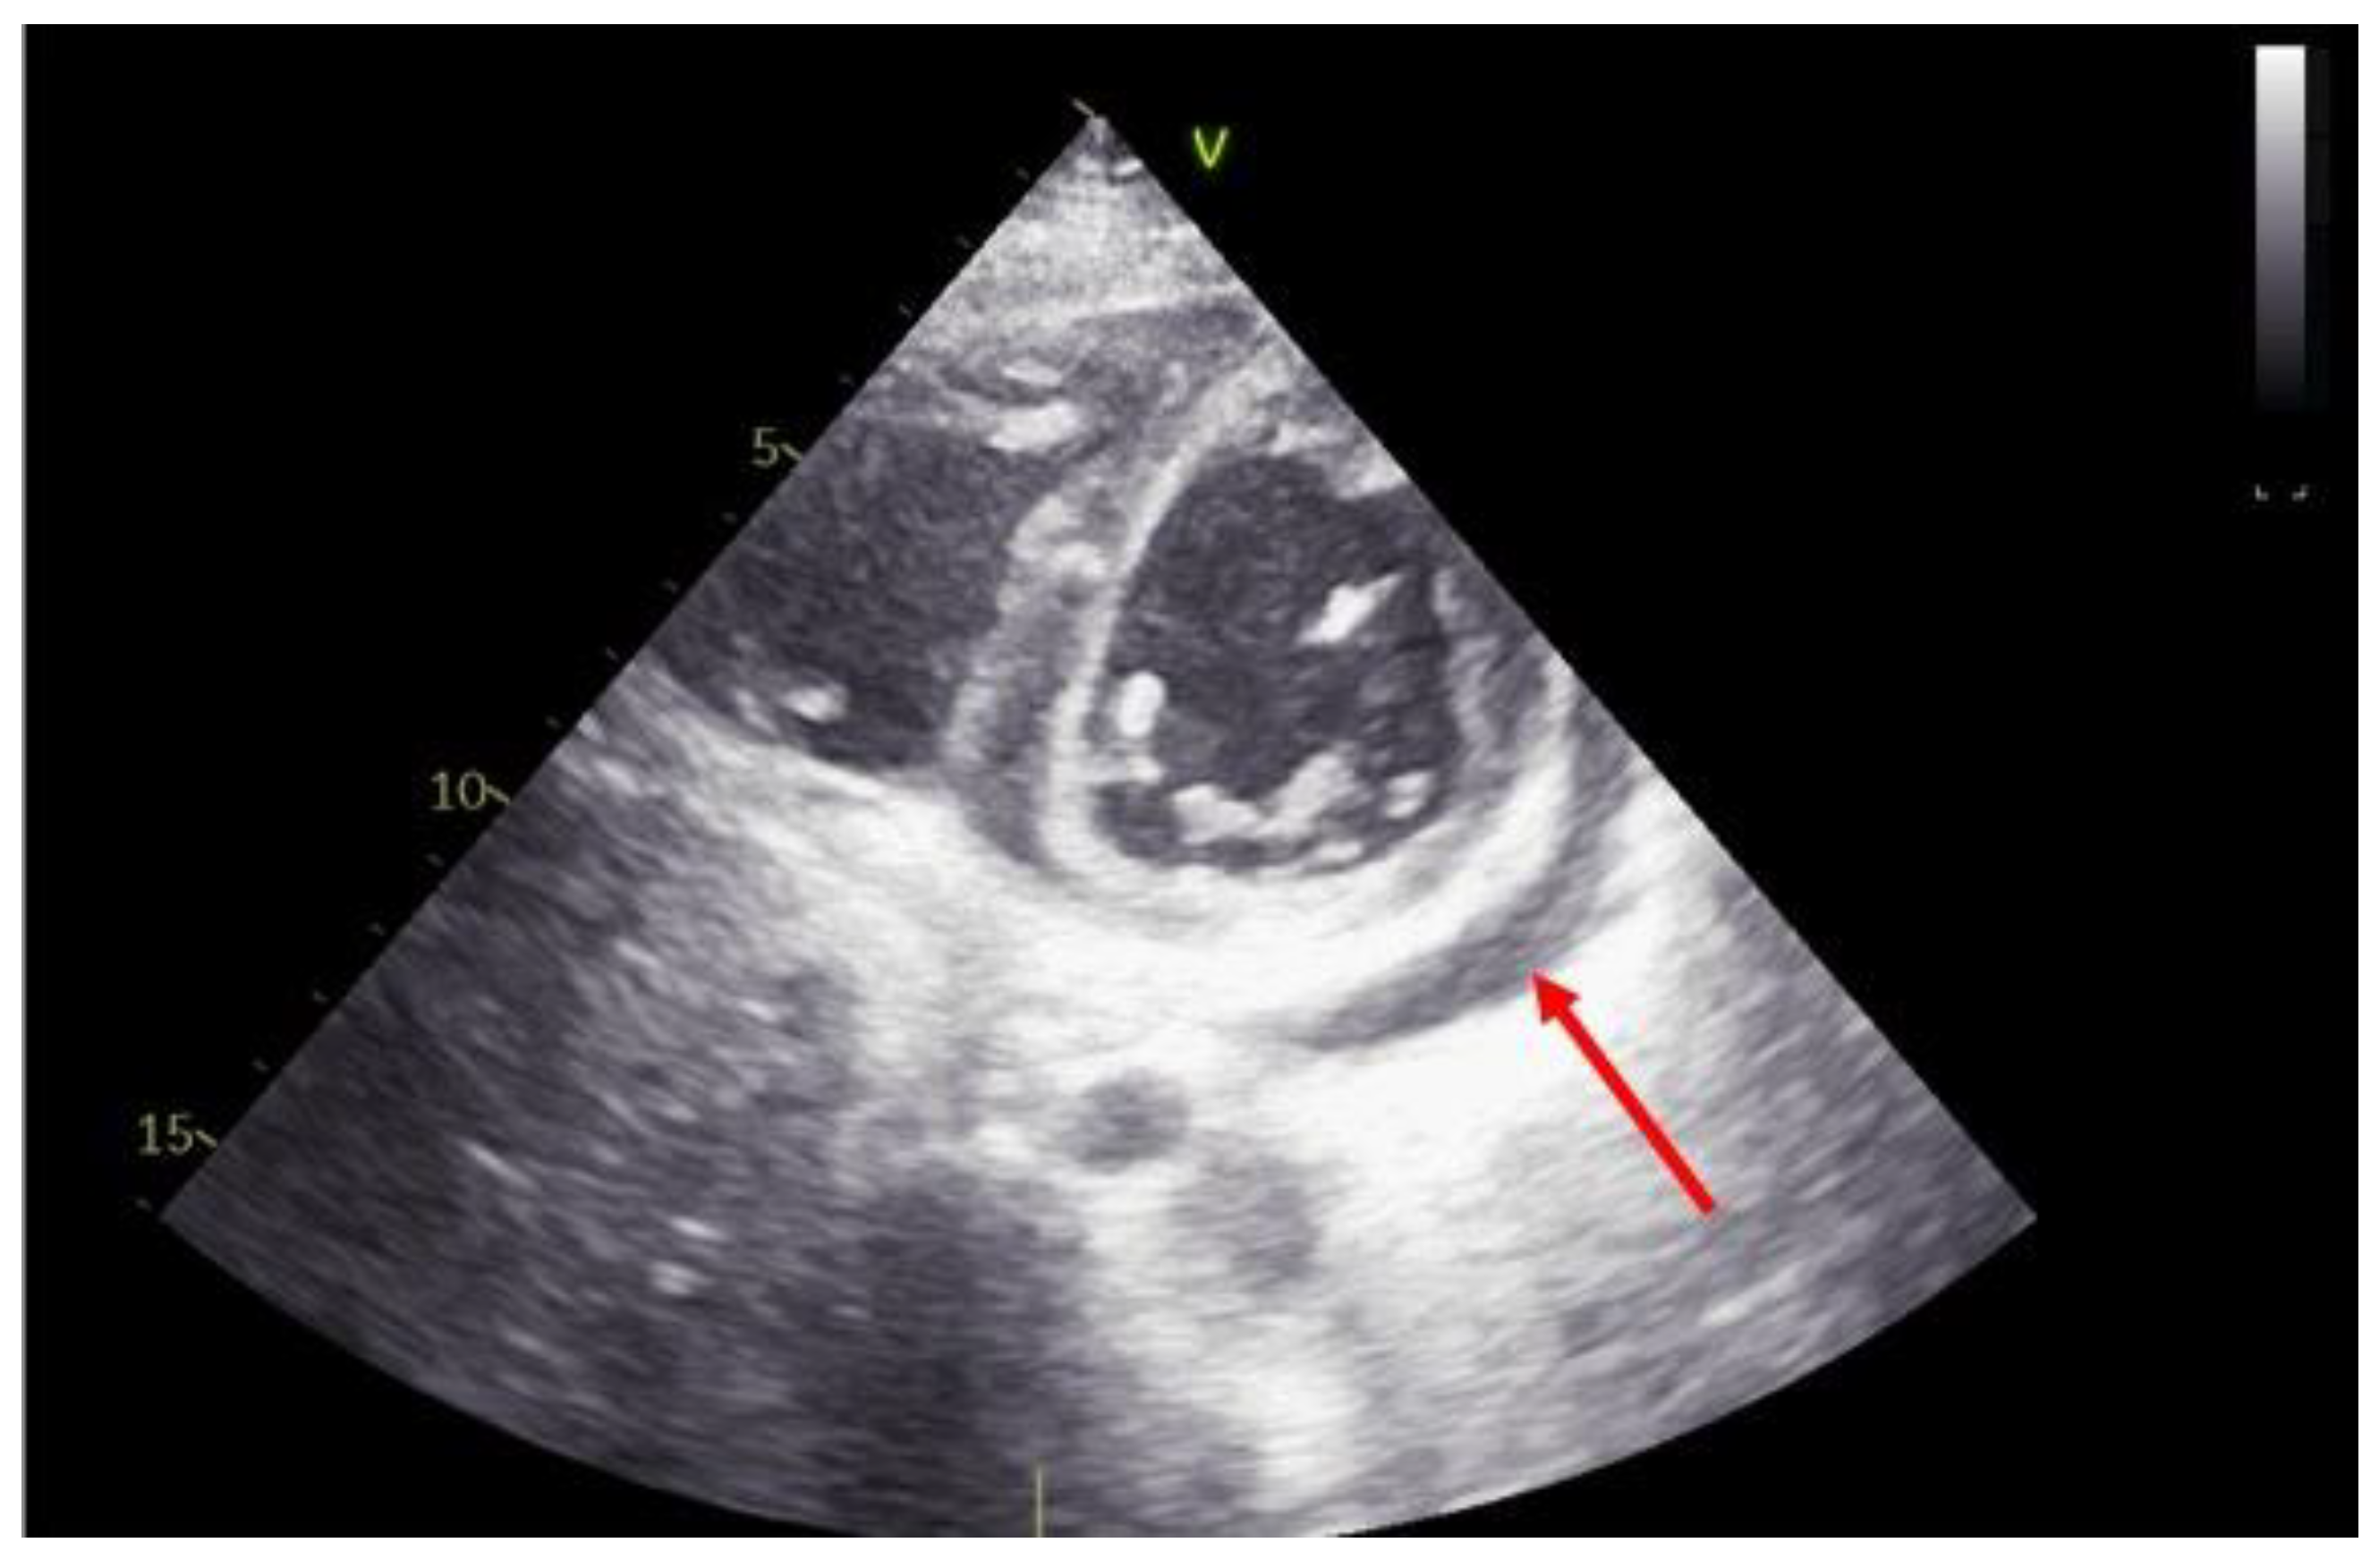

3. Role of Echocardiography in the Evaluation of Primary Graft Dysfunction

4. Role of Echocardiography in the Evaluation of Acute Graft Rejection